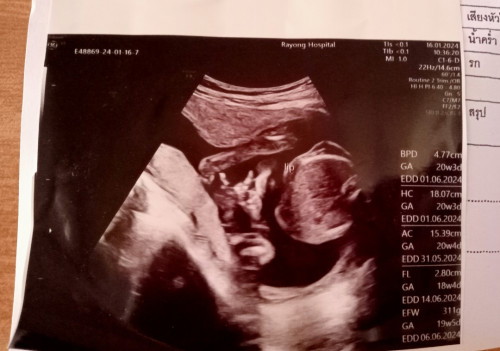

20wแล้ว แต่ยังไม่รู้เพศลูก หาหมอที่ รพ.รัฐ แต่หมอไม่ได้อัลตร้าซาวด์ดูเพศให้ ปกติเขาจะดูให้ไหมค่ะ หรือต้องไปเสียตังค์ดูเองที่คลินิก แต่ความรู้สึกแม่บอกว่าเป็นผู้ชาย คนรอบข้างบอกถ้าความรู้สึกแม่บอกอย่างนั้นก็ผู้ชาย แต่ก็มีคนทักว่าเป็นผู้ชายเยอะมาก#ขอบคุณสำหรับคำตอบค่ะ #ท้องแรกคะ

กำลังตั้งครรภ์